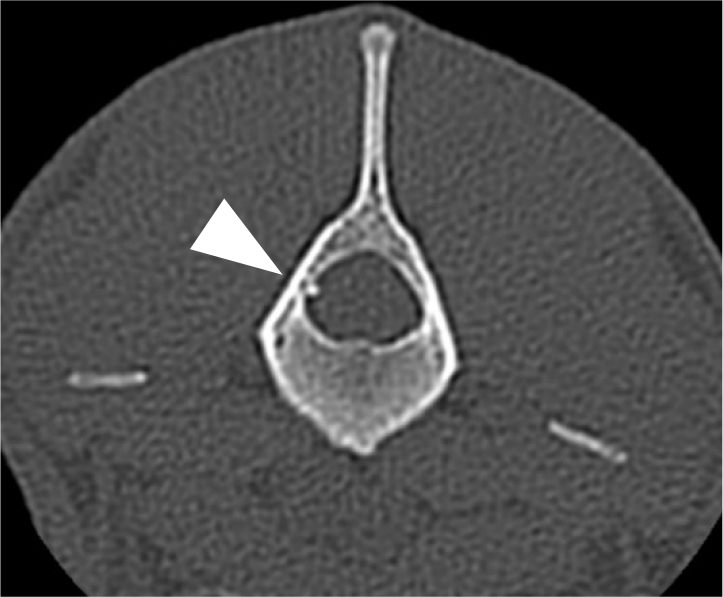

Material and methods: This is prospective cross-over experimental study. Five healthy adult beagle dogs were anaesthetised and an epidural catheter was inserted in the lumbosacral area and adjusted so that the end of the catheter was placed at the fourth lumbar vertebra. Single-port catheters were used in the control group and multiple-port catheters were used in the treatment group. A PI probe was placed on a hind leg, and the catheter placement was confirmed via computed tomography. The treatment group received a bolus dose of lidocaine, and the control group received saline, via epidural catheter. The PI value was recorded every 5 min until 30 min after lidocaine injection.